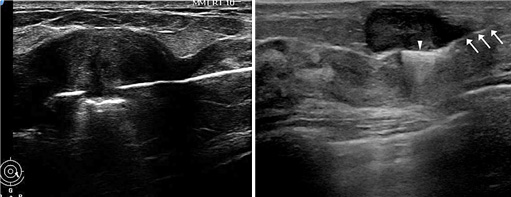

2. 유방초음파

인체에 전혀 해롭지않은 초음파검사는 유방에 멍울이 있을 때 진단을 쉽게 내릴 수 있습니다. 특히 40세미만 여성인 경우, 맘모그래피에서는 소위 고밀도 치밀유방(유방의 젖샘조직밀도가 높아서 맘모그래피영상에서 보면 흰색부분이 많거나 진하게 보이는 유방)에 혹(멍울)이 있는지 여부를 확인할 수 없습니다.

그러나 초음파검사에서는 치밀유방을 갖는 어느 경우에도 혹(멍울)을 영상으로 잡아낼 수있고, 모양과 경계부양상, 부드러움과 거칠음 등을 통해 양성인지 악성인지를 감별할 수 있습니다.

생검과정은 해상능력이 좋고 인체에 해가 없는 주파수가 높은 초음파를 보면서 병변을 확인하며 모든 과정을 초음파유도하에 병변내에 생검주사침이 정확히 targeting하도록 합니다.

유방초음파를 보면서 병변부위를 확인하고 병변주위 초음파 탐촉자를 중심으로 광범위하게 피부를 소독제솜으로 씻어내고,수술포를 넓게 깔아 줍니다.

초음파 탐촉자와 부속물을 소독제솜으로 반복하여 닦아주고 나서,다시 초음파를 하여 병변을 확인하고 초음파를 그대로 병변위에 유지한 채 주사침이 들어갈 피부와 유방조직에 국소마취를 시행합니다.

초음파에 보인 영상으로 침위치가 잡히면 스위치를 켜고, 유방조직샘플을 채취하게 되는데 이때 "윙윙"거리거나 또는 "딸깍딸깍"하는 소리가 납니다.